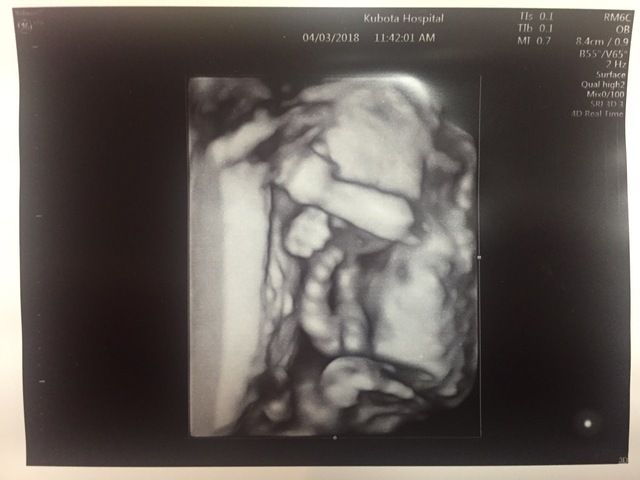

19週3日(19w3d・女の子)|すけろく さん(32歳)

エコー写真撮影時のエピソード:

だいぶお腹が大きくなってきて、服によっては妊婦さんとわかるようになってきた頃です。ムカムカしたり、日によって食べれるものが違ったり、食べ過ぎたりしていたつわりも少し収まって普通の食事ができるようになってきた頃で体調は落ち着いていました。お父さんはいつも検診に行っていましたが、いつも顔を見せてくれて嬉しそうでした!この頃から骨がしっかりしてきて肋骨が立派に見えるのがこの写真のお気に入りポイントです。

このしばらく後に転居し、4Dエコーをやってくれない病院になってしまったので顔がはっきり見られなくなって残念です。